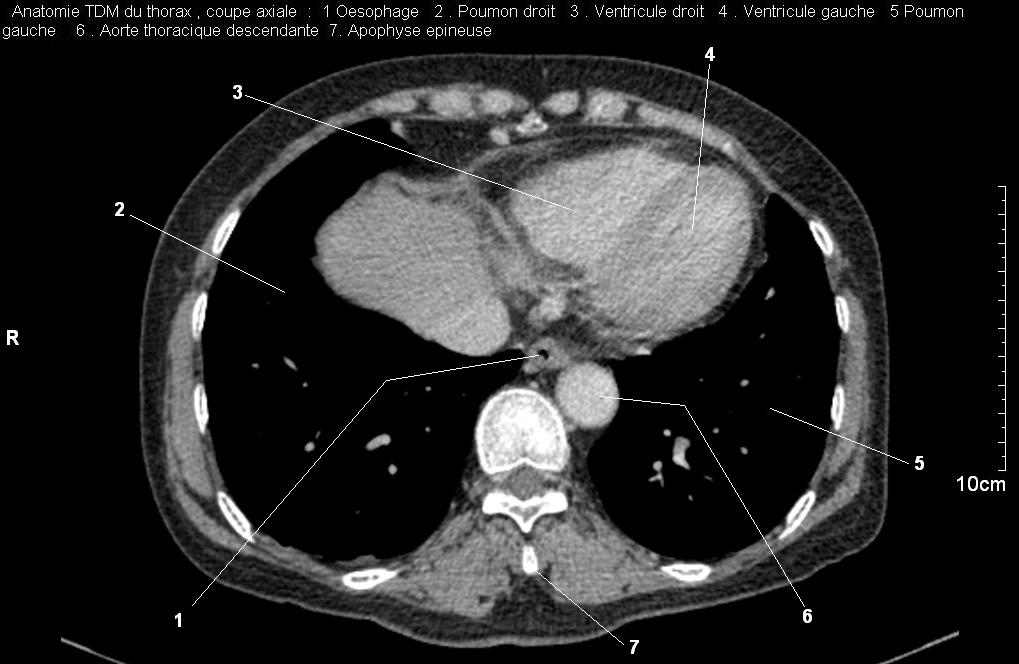

Radioanatomie pulmonaire ( image radiologie thoracique normale )- La Tomodensitometrie du  thorax ( coupes axiales fenetre mediastinale )

Les fenetres mediastinales permettre d'etudier anatomie du mediastin et les structures vasculaires en coupes axiales de 0,5-1cm sur le thorax . Et si elles sont opacifiees par produit de contrast elles sera se donnent des resutats suivantes :